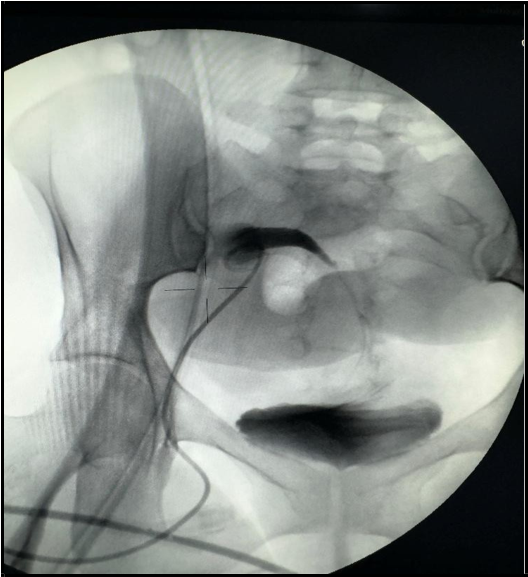

Upon presentation to our emergency department, her vital signs were notable for hypertension (BP 216/118 mmHg) and tachycardia (HR 109 bpm), though she remained afebrile and maintained oxygen saturation of 100%. Physical examination revealed ecchymosis over the right lower quadrant at the surgical site. Laboratory investigations showed severe anemia (Hb 7 g/dL), thrombocytopenia (66 × 10⁹/L), and serum creatinine (68 µmol/L). Abdominal ultrasound demonstrated preserved perfusion of the graft with patent main renal vessels. However, there was a significant increase in resistive index (RI) values within the intrarenal arterial branches, with areas showing a monophasic wave pattern, suggestive of impaired intrarenal flow and warranting close follow-up [Figure 1]. Additionally, elevated velocity at the main renal artery anastomosis site was noted, likely reflecting postoperative changes. A peri-graft fluid collection was identified, with the largest pocket measuring approximately 74 mL, requiring ongoing monitoring for potential complications.

Figure 1: Doppler showing elevated intrarenal resistive index with monophasic waveforms, suggesting impaired intrarenal flow (RI = 0.91).